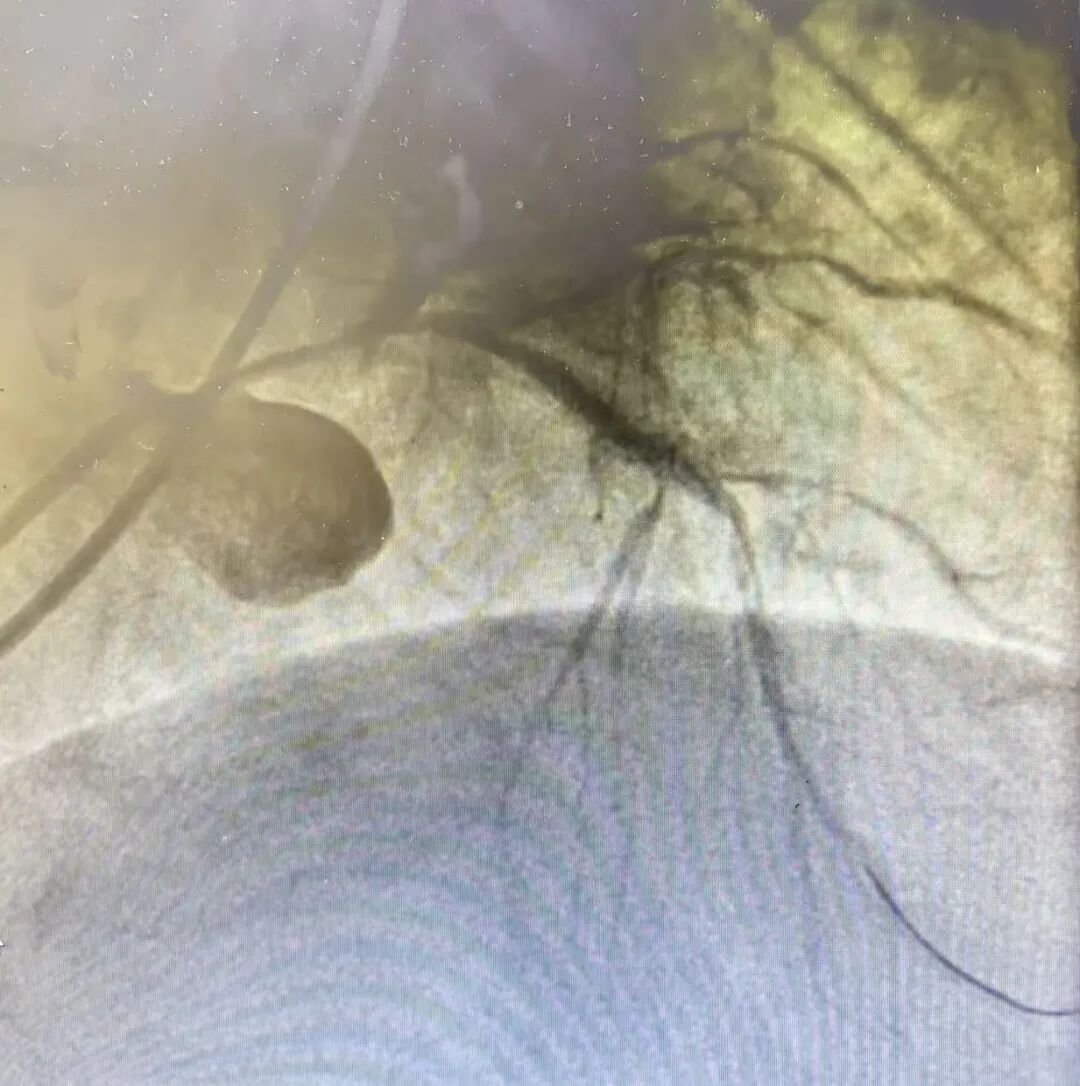

术中,在血管内超声的精准引导下,唐忠仁主任团队精细操作导管、导丝、球囊,在极度狭窄的血管中“精雕细琢”,最终成功打通堵塞血管。

当硬核技术遇上患者的信任,每一份托付都掷地有声。在IVUS指导下,当左主干至前降支处成功植入支架,瞬间打通堵塞血管、恢复血流,将许先生从死亡线上拉了回来。